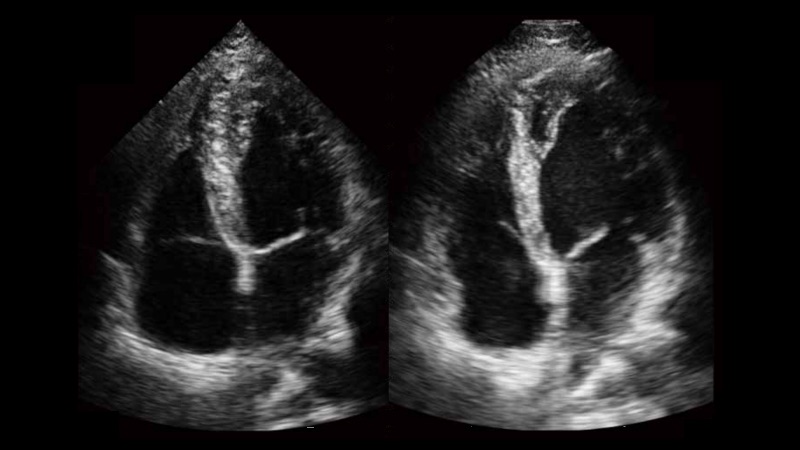

自動(dòng)識(shí)別收縮和舒張末期心肌內(nèi)膜,自動(dòng)計(jì)算射血分?jǐn)?shù)EF值。